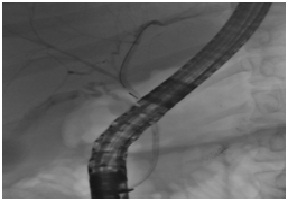

Giant Portal Vein Extra Hepatic Aneurysm: An Uncommon Finding

MartÃn MS et al.

Journal of Digestive Diseases and Hepatology